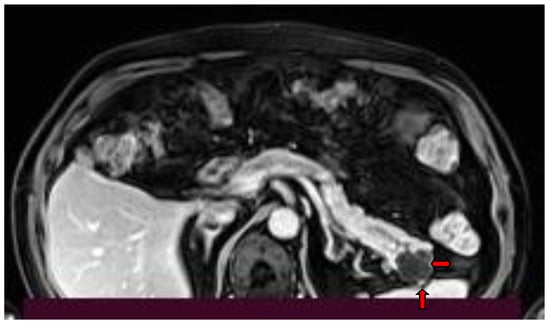

2. Imaging Findings